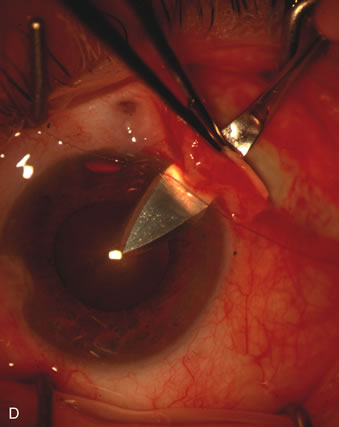

Fig. 1. The anatomic advantage of small incision cataract surgery for the glaucoma patient. A. Long-term bleb function with a large cataract incision is difficult to achieve with either ECCE-trabeculectomy or trabeculectomy followed later by ECCE. This bleb failed to form sufficiently when combined with large incision ECCE. The inflammation, bleeding, and long-term wound healing with stimulation of fibroblasts associated with this technique are more likely to cause bleb failure. In addition, the increased iris manipulation necessary to deliver the nucleus and subsequent iris repair adds to the long-term breakdown of the blood aqueous barrier. B and C. Two-site phacotrabeculectomy has the advantage of small incision cataract surgery combined with separate site trabeculectomy. The incision size is one third the size of the standard ECCE. The inflammation is less severe, and cataract wound healing is confined to the temporal area. Visual rehabilitation with phacoemulsification and foldable IOL is much faster. Phacoemulsification allows successful lens extraction even in the unfriendly environment of a smaller pupil compared with ECCE. The trabeculectomy is performed in an entirely different site, well away from the wound healing associated with temporal phacoemulsification. The likelihood of this filter functioning long-term is greater than with ECCE-trabeculectomy. D. The surgeon also has the option of single-site phacotrabeculectomy with foldable IOL. Both the lens extraction and trabeculectomy are performed through one small 3.5-mm limbal incision.

Fig. 3. Partial bleb failure following clear corneal phacoemulsification with foldable IOL. A. Preoperative bleb appearance prior to temporal lens extraction. Preoperative IOP was 12 mm Hg on no antiglaucoma medications. Time from 5-FU trabeculectomy surgery to lens extraction was one year. B. Bleb appearance 2 months after clear corneal cataract surgery with topical anesthesia. Following lens extraction, increased vascularity was noted along with decreased size of the filtering bleb. IOP increased to 20 mm Hg as early as 2 weeks after surgery, necessitating topical antiglaucoma therapy. C. High magnification view of bleb before lens extraction demonstrates diffuse pale bleb. D. High magnification view of bleb 2 months after surgery. There are vessels surrounding the nasal side of the bleb and the overall bleb size is smaller.